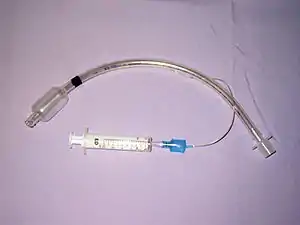

Certain medical procedures can also injure the airways; these include tracheal intubation, bronchoscopy, and tracheotomy.[4] The back of the trachea may be damaged during tracheotomy.[18] TBI resulting from tracheal intubation (insertion of a tube into the trachea) is rare, and the mechanism by which it occurs is unclear.[19] However, one likely mechanism involves an endotracheal tube catching in a fold of membrane and tearing it as it is advanced downward through the airway.[20] When an endotracheal tube tears the trachea, it typically does so at the posterior (back) membranous wall.[17] Unlike TBI that results from blunt trauma, most iatrogenic injuries to the airway involve longitudinal tears to the back of the trachea or tears on the side that pull the membranous part of the trachea away from the cartilage.[20] Excessive pressure from the cuff of an endotracheal tube can reduce blood supply to the tissues of the trachea, leading to ischemia and potentially causing it to become ulcerated, infected, and, later, narrowed.[4]

Treatment of TBI varies based on the location and severity of injury and whether the patient is stable or having trouble breathing,[2] but ensuring that the airway is patent so that the patient can breathe is always of paramount importance.[10] Ensuring an open airway and adequate ventilation may be difficult in people with TBI.[3] Intubation, one method to secure the airway, may be used to bypass a disruption in the airway in order to send air to the lungs.[3] If necessary, a tube can be placed into the uninjured bronchus, and a single lung can be ventilated.[3] If there is a penetrating injury to the neck through which air is escaping, the trachea may be intubated through the wound.[10] Multiple unsuccessful attempts at conventional (direct) laryngoscopy may threaten the airway, so alternative techniques to visualize the airway, such as fiberoptic or video laryngoscopy, may be employed to facilitate tracheal intubation.[10] If the upper trachea is injured, an incision can be made in the trachea (tracheotomy) or the cricothyroid membrane (cricothyrotomy, or cricothyroidotomy) in order to ensure an open airway.[6] However, cricothyrotomy may not be useful if the trachea is lacerated below the site of the artificial airway.[10] Tracheotomy is used sparingly because it can cause complications such as infections and narrowing of the trachea and larynx.[26] When it is impossible to establish a sufficient airway, or when complicated surgery must be performed, cardiopulmonary bypass may be used—blood is pumped out of the body, oxygenated by a machine, and pumped back in.[26] If a pneumothorax occurs, a chest tube may be inserted into the pleural cavity to remove the air.[12]